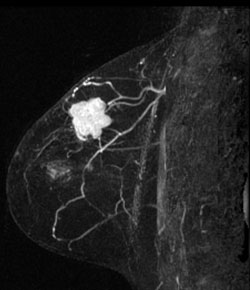

A right breast invasive lobular cancer (Estrogen Receptor/Progesterone Receptor +, Her-2 neu -).

MIP (Maximum Intensity Projection) image of MR

MIP (Maximum Intensity Projection) image of MR shows the known cancer: irregularly marginated mass in the upper outer to central breast. Satellite subcentimeter nodules are present anteromedially and posteriorly.